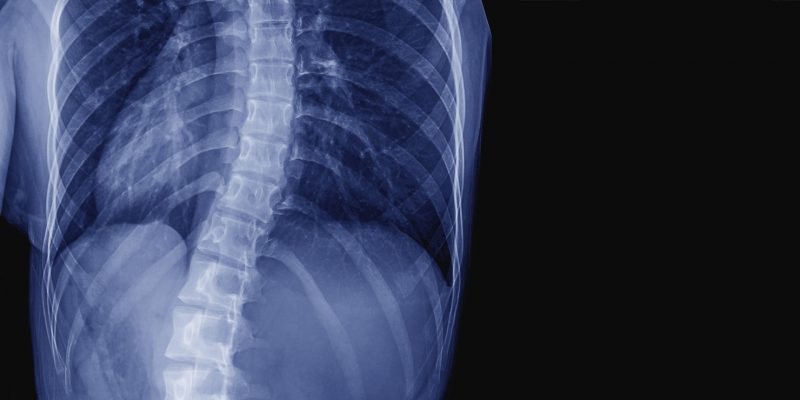

Scoliosis refers to a curvature of the spine in all three planes – side to side, front to back and rotating. As the spine curves and twists, it turns the ribcage round and this changes the shape of the body.

The curvature can occur in any part of the spine, or in more than one part. The most common regions affected are the chest area (thoracic scoliosis) and the lower part of the back (lumbar scoliosis) or a combination of both.

A detailed history will be taken from birth to the present time. You will have a physical examination where the surgeon looks for the features mentioned previously, your posture, your reflexes and muscle power. X rays are taken initially and then regularly to monitor curve progression. These determine the type of curve, its position and direction. The angle of curves can be measured and treatment determined accordingly.

X rays and physical appearances also help the surgeon determine how close you are to skeletal maturity and therefore to assess how likely the curve is to progress. An MRI (magnetic resource imaging) scan may also be requested to rule out any underlying neurological or bony conditions, or rare causes of scoliosis.